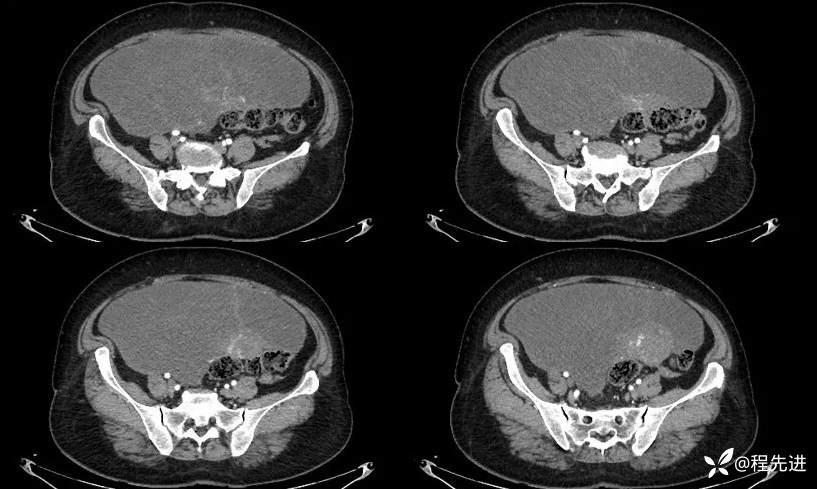

门脉期: